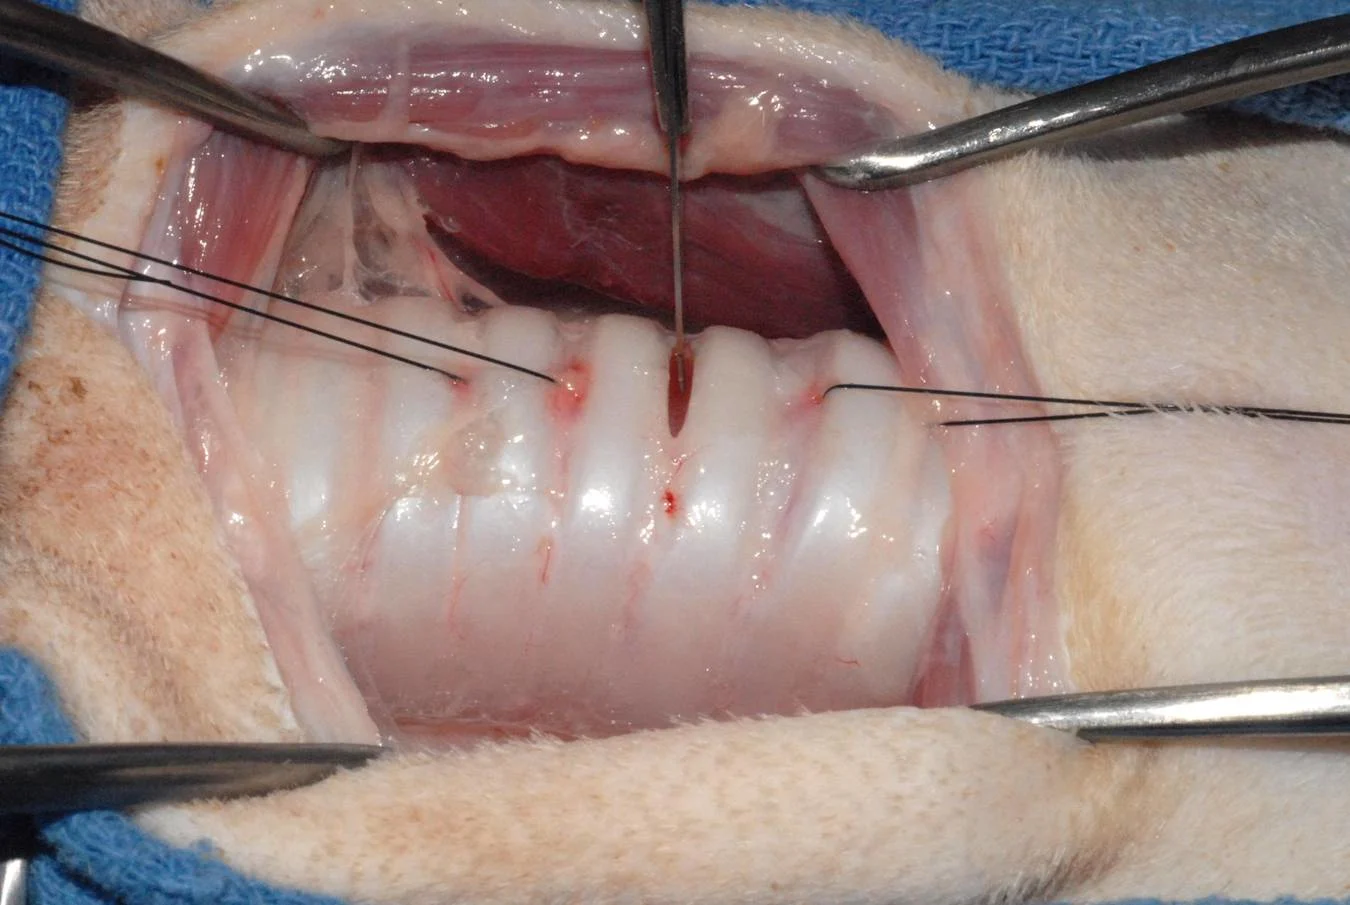

Step 6

Two stay sutures (2/0 monofilament nylon) are placed above and below the intended incision site and are tied as long loops (8 to 10 cm). These stay sutures aid in manipulation of the tracheal stoma. Before this is done, check the location of the endotracheal tube (if one is in place) to avoid snagging the inflated cuff with the stay sutures. It may also be helpful to accentuate the curvature of the suture needle (ie, bend it) before placing the stay sutures. This is especially true when using a flatter needle (3/8 curvature) normally associated with skin sutures. The stay sutures can be used to pull the stoma apart when the tracheostomy tube is changed or replaced.

Step 7

The actual tracheostomy can be performed by several different techniques. I prefer to make a horizontal incision between tracheal rings 3 and 4 or 4 and 5. The incision extends roughly 40% to 50% of the circumference of the trachea. Again, care is taken to avoid iatrogenic injury to structures on the sides of the trachea.